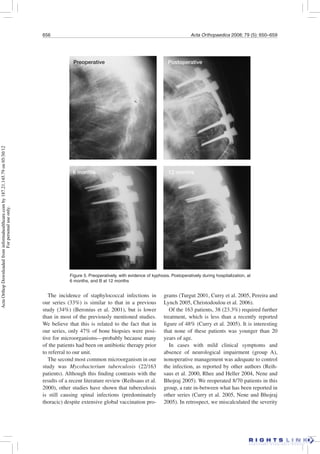

Figure 5. Preoperatively, with evidence of kyphosis. Postoperatively during hospitalization, at

6 months, and B at 12 months

Preoperative Postoperative

6 months 12 months